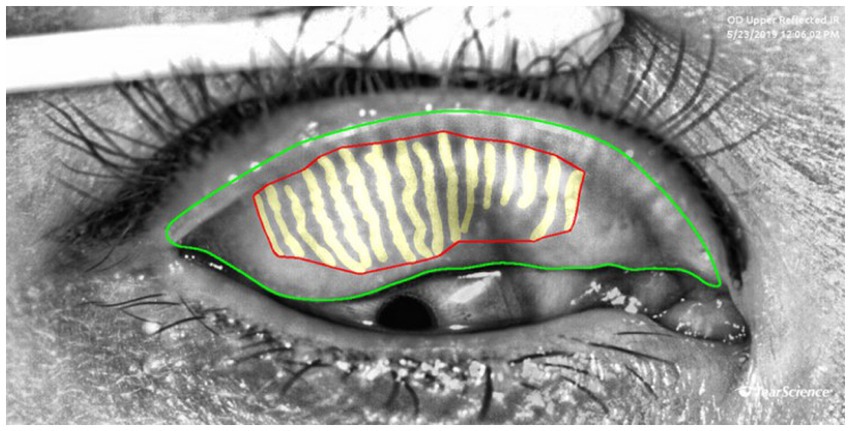

Gland area represents the actual coverage of glands. A reduction in area indicates gland atrophy or loss, which is directly linked to decreased tear film stability. It is calculated by summing the areas of the outer boundaries of each gland, as shown by the yellow region in Figure 3. Gland density is calculated by dividing the total MG area by the tarsal region area, reflecting the abundance of glands per unit area. A decrease in density is a macroscopic manifestation of gland degeneration. Loss ratio refers to the proportion of missing gland area relative to the total tarsal area. It is calculated by subtracting the sum of all gland areas from the tarsal contour area and then dividing by the tarsal contour area. This index quantitatively evaluates the degree of gland loss by comparing the gland area with the entire tarsal area, serving as a core parameter for MGD diagnosis and treatment efficacy assessment.

Figure 3. Examples of measurement of the area, density and loss ratio of the glands: the red area represents the gland area, gland density is calculated as the red area divided by the area enclosed by the green lines, The gland loss ratio is computed as the quotient of (the area bounded by the green contours minus the red contours) divided by the area bounded by the green contours.